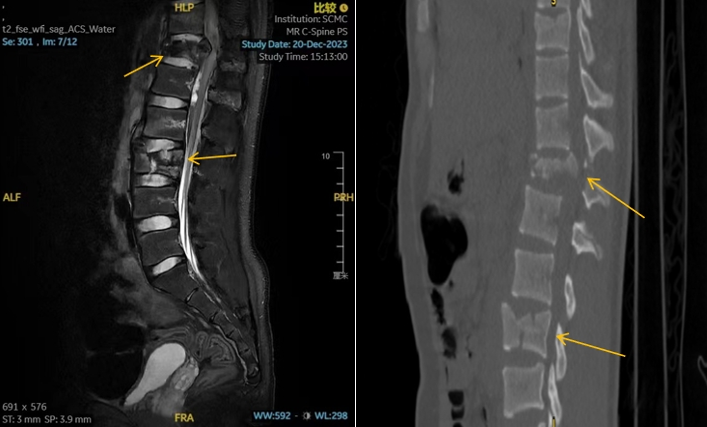

当时他虽意识清醒,但双下肢已无法站立,感觉麻痹。家属立即拨打120将孩子送至上海交通大学医学院附属上海儿童医学中心急诊。入院后, CT结果提示其胸、腰椎多发爆裂骨折,情况十分危急。

术前CT显示,孟迪的胸、腰椎多发爆裂性骨折伴移位。 本文图均为上海儿童医学中心供图